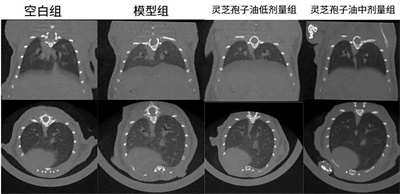

靈芝孢子油對肉芽腫型肺結(jié)節(jié)小鼠肺部斷層掃描檢測結(jié)果

靈芝孢子油對肉芽腫型肺結(jié)節(jié)小鼠肺部斷層掃描檢測結(jié)果統(tǒng)計

體內(nèi)功效實驗研究結(jié)果表明:在為期52天的小鼠實驗中,每日6粒廣藥牌靈芝孢子油,靈芝孢子油顯著減少了肺部肉芽腫結(jié)節(jié)的面積(減少23.07%)和磨玻璃陰影,降低炎癥因子和趨化因子水平,證實廣藥牌靈芝孢子油具有一定的防治小鼠肉芽腫型肺結(jié)節(jié)的作用。